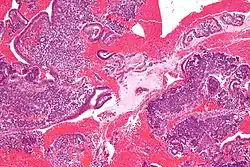

Endometrioid adenocarcinoma from biopsy. H&E stain. -